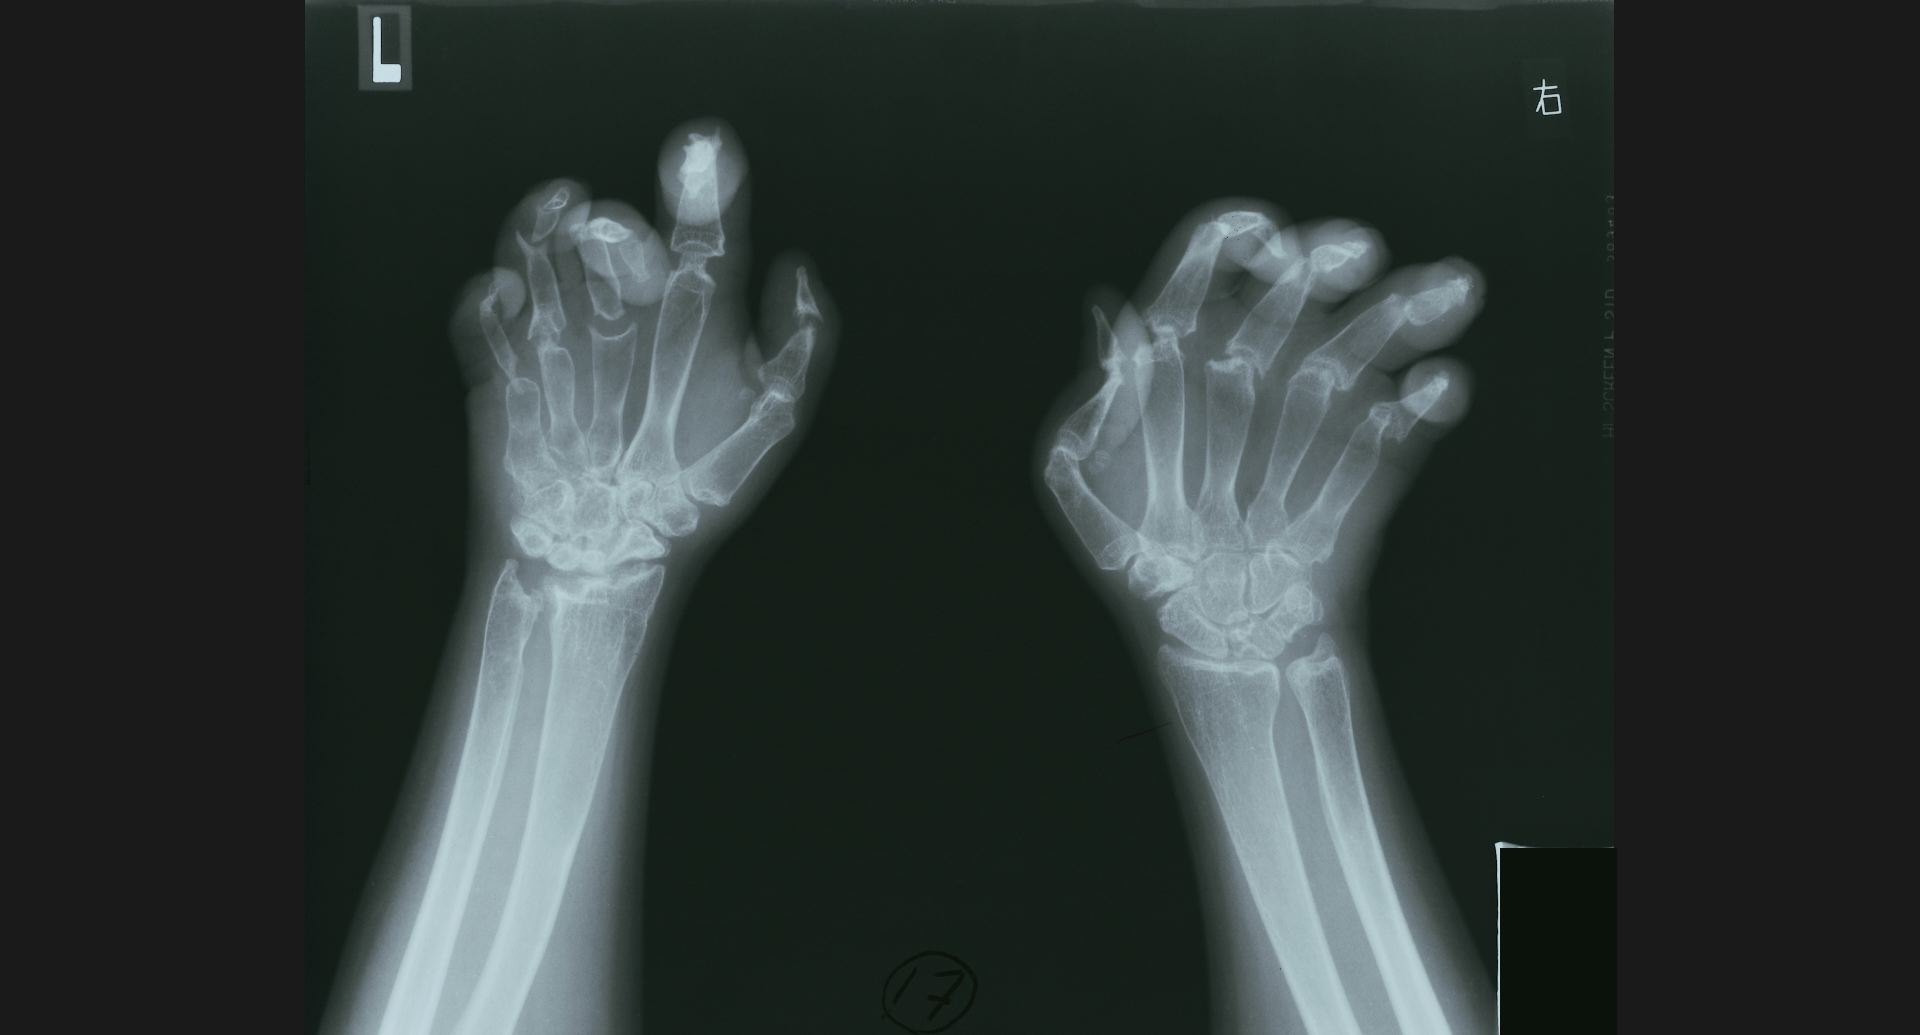

:Acro-osteolysisradius遠位端の骨梁。骨融解部。

fig.18(70KB)